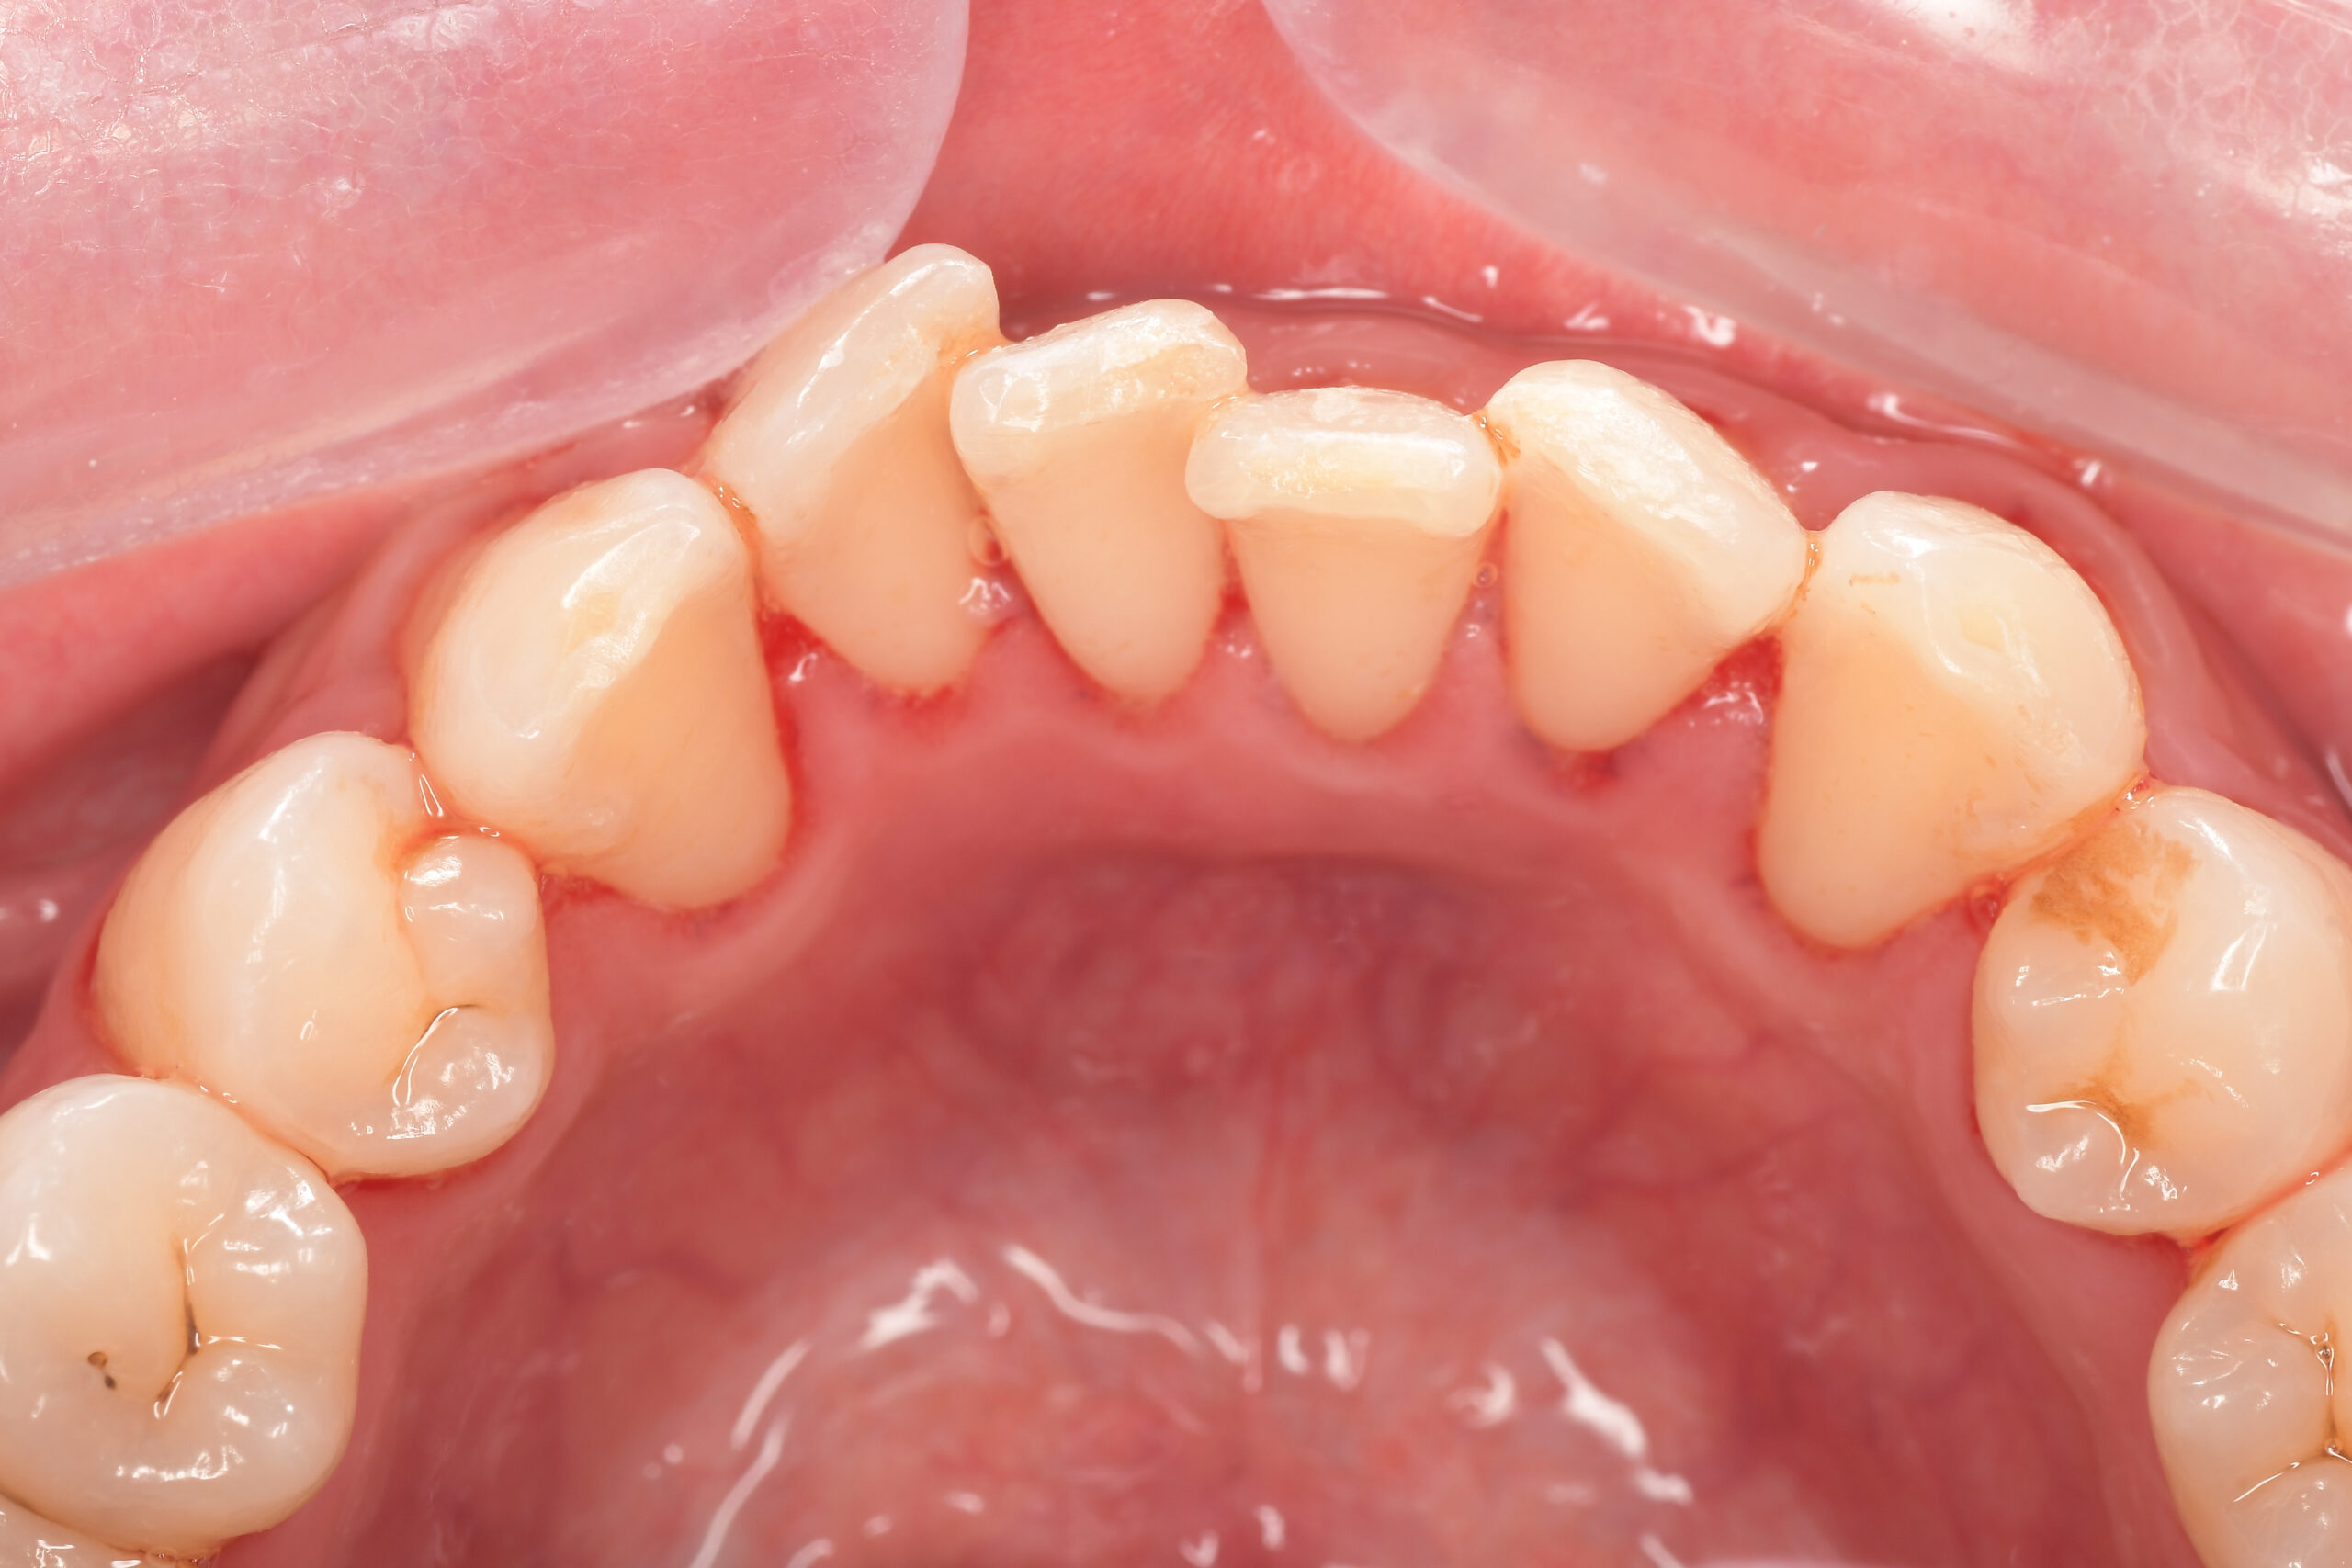

CASE 14

下顎before

下顎after

臼歯before

臼歯after

基本情報

| 年齢・性別 | 27歳・男性 |

| 主訴 | 歯石とりたい |

| 治療内容 | スケーリング |

| 治療期間 | 30分 |

| 治療費 | 約1,500円(保険診療) |

| リスク・副作用 | 知覚過敏、歯肉退縮、出血 |

| 治療方針 | 歯列不正でプラークがつきやすいため、TBIを行い定期的に歯石を除去していきます。 プラークコントロールが出来るようになったら定期検診でクリーニングを行っていきます。 |